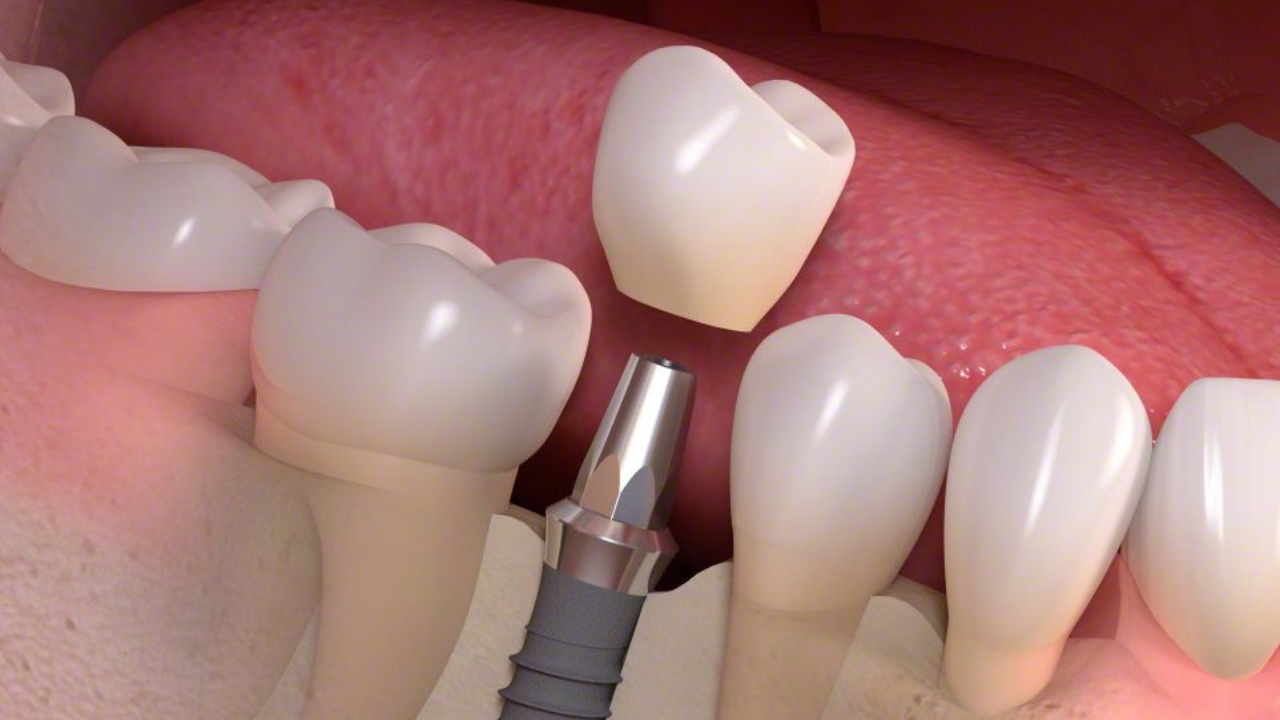

รากฟันเทียมอยู่ได้นานแค่ไหน

การสูญเสียฟันแท้ไปอาจไม่ใช่แค่เรื่องของความสวยงามที่หายไปเท่านั้น แต่มันส่งผลกระทบต่อประสิทธิภาพในการบดเคี้ยวอาหาร ความมั่นใจในการพูด และโครงสร้างโดยรวมของช่องปากในระยะยาว นวัตกรรมการรักษารากฟันเทียมจึงก้าวเข้ามาเป็นคำตอบที่ดีที่สุดสำหรับผู้ที่ต้องการฟื้นฟูรอยยิ้มให้กลับมาสมบูรณ์แบบอีกครั้ง แต่หนึ่งในคำถามที่คนไข้มักจะสงสัยและเป็นกังวลมากที่สุดคือเมื่อทำไปแล้ว รากฟันเทียมอยู่ได้นานแค่ไหน และมันคุ้มค่ากับการลงทุนในเรื่องของราคาและเวลาจริงหรือไม่ หากจะตอบคำถามนี้แบบตรงไปตรงมา รากฟันเทียมถูกออกแบบมาเพื่อให้เป็นการรักษาแบบกาวาล์วหรือถาวร ซึ่งหมายความว่ามันมีศักยภาพที่จะอยู่กับเราไปได้ตลอดชีวิต ต่างจากฟันปลอมแบบถอดได้หรือสะพานฟันที่มีอายุการใช้งานจำกัดเพียงไม่กี่ปี อย่างไรก็ตาม คำว่าตลอดชีวิตนี้ไม่ได้เกิดขึ้นได้เองโดยอัตโนมัติ แต่ต้องอาศัยปัจจัยหลายอย่างประกอบกัน